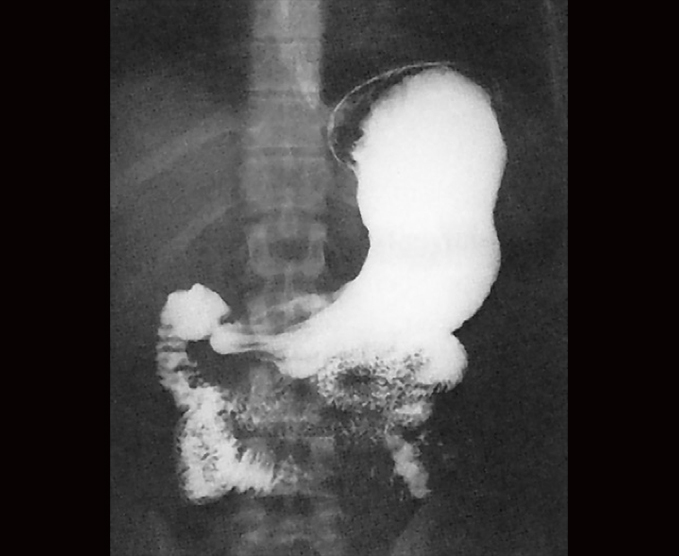

Algunos de nuestros estudios contrastados.

- Serie esófago gastroduodenal